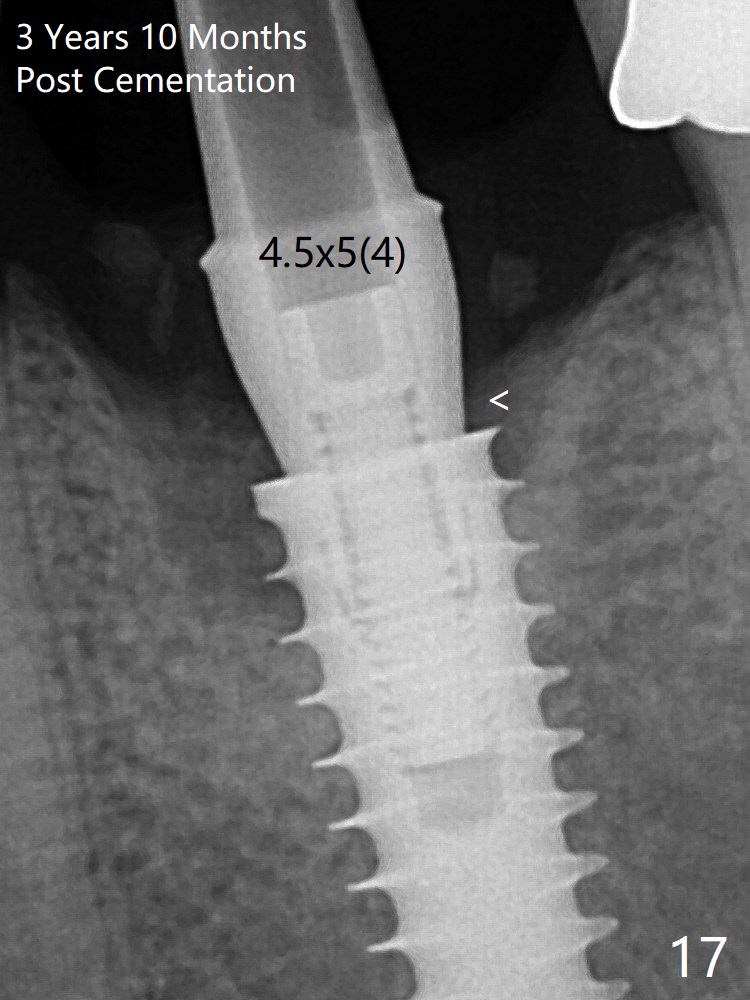

The crown/abutment is loose 3 times (3 months (Fig.14), 11 months (between Fig.14 and 15) and 2 years 3 months post cementation). In spite of being stable 3 years 10 months post cementation, a smaller abutment is placed (Fig.17 (PA), 18 (BW)) with impression for a new crown.